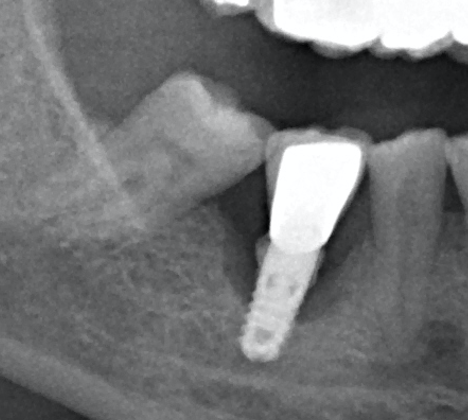

El implante del 46 no se cual es

Hola a todos, Voy a realizar una cirugía regenerativa en el implante del 46 , no se que implante es y necesito saberlo para localizar el tornillo de cierre, su [...]

Este paciente acude a nosotros porque desde que le colocaron la corona hace dos años se le afloja cada dos o tres meses. No nos facilitan la información del implante [...]

Buenas tardes: Tengo una auxiliar de las clínicas en la que trabajo, que le pusieron este implante hace 7 años aproximadamente, la clinica en la que se la pusieron han [...]